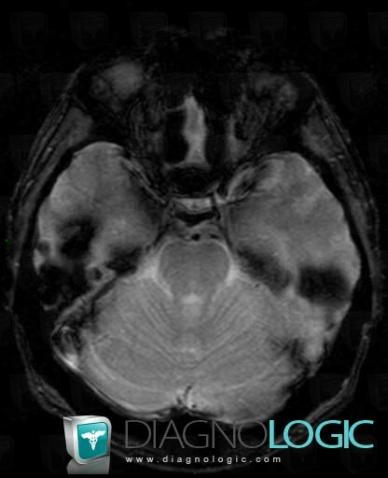

Le diagnostic repose sur l'imagerie médicale comme l'imagerie à résonance magnétique et l'examen pathologique en cas d'intervention chirurgicale.